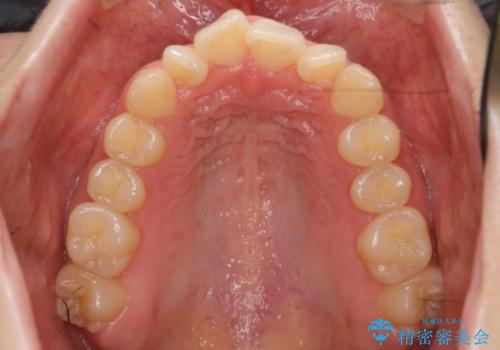

歯を抜かずに奥歯を後ろに下げてマウスピースで矯正しています。

上の奥歯を後ろに下げて前歯のねじれを治すスペースを確保しました。

奥歯を後ろに下げるために、矯正用インプラントを使用しています。